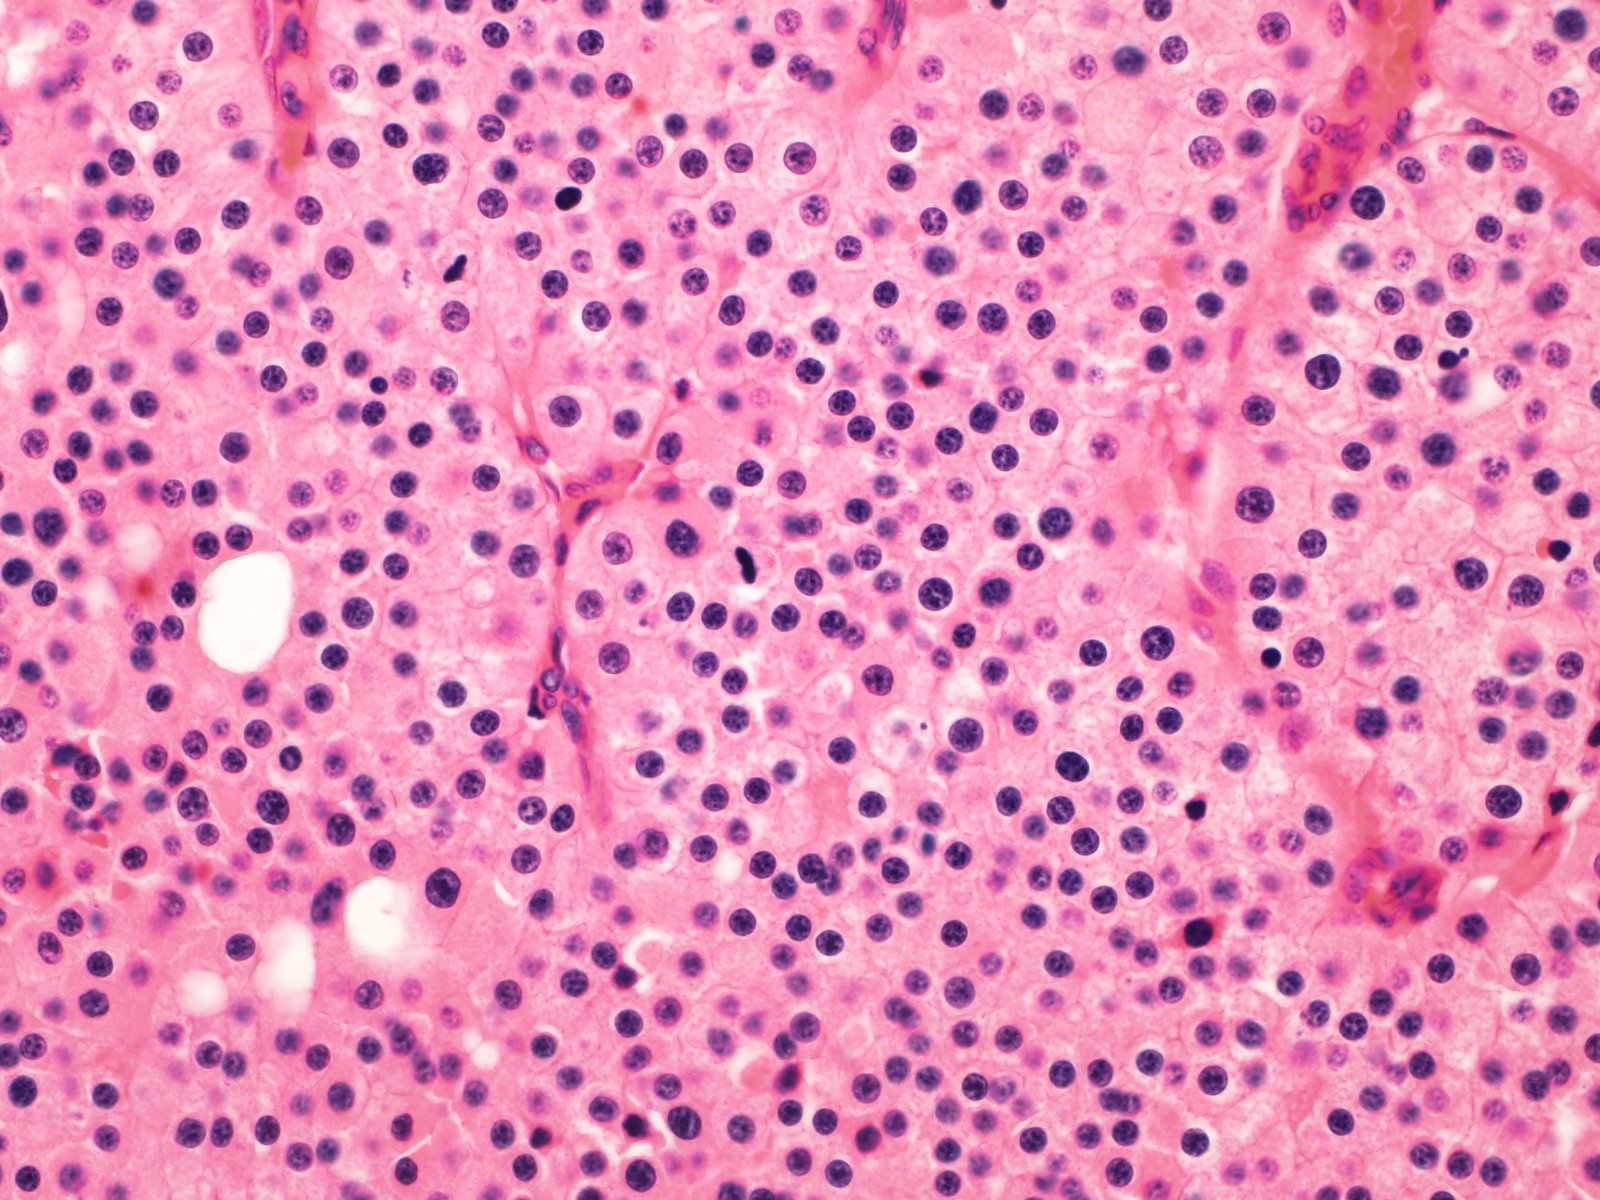

Case ID: 819

Consensus grade: I would not grade this tumor

chromophobe |

chromophobe RCC-grading? |

Case description (by case creator):